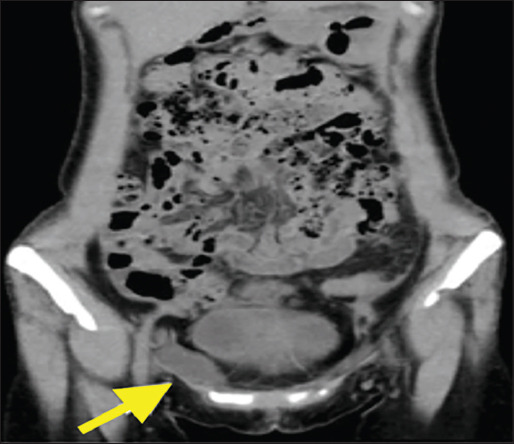

Case report: A 43-year-old female patient, presented to our hospital with a five-year history of swelling and slight discomfort in the right groin. A nonreducible inguinal mass with greater projection during a Valsalva maneuver was found. An abdominal CT scan revealed a well-defined lesion located near the right horn of the uterus and extending through the inguinal canal. The patient was brought to the operating room with the clinical suspicion of an inguinal hernia. A soft mass measuring 4.5×2×1.8cm was discovered in the right round ligament, and it was surgically removed. Histopathological examination confirmed a mesothelial cystic lesion. The patient's condition, after a period of 12 months, continues to be satisfactory.